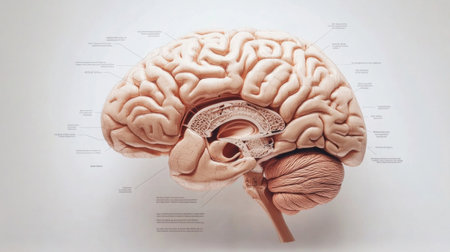

This detailed cross-section of the human brain illustrates its anatomical features, making it ideal for educational purposes in neuroscience and medicine.

An educational scene featuring a human brain cross-section with labeled parts, alongside medical charts and anatomical references for a classroom setting.

An educational diagram of the human brain with major parts and functions labeled, set against a simple white background for clear, informative presentation.